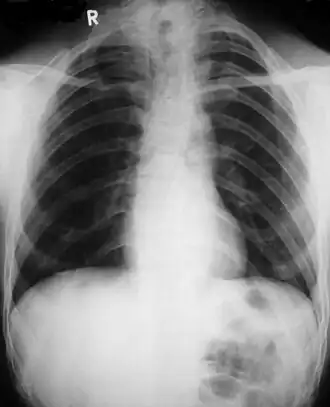

Диагностика ключично-черепного дизостоза основана на клинических симптомах и рентгенологических исследованиях, которые включают изображения черепа, грудной клетки, таза и рук. Главный рентгенологический симптом — дефекты ключиц. Обычно отсутствует наружный (акромиальный) конец ключицы, в то время как внутренний (грудинный) конец присутствует. Но иногда ключица состоит из двух фрагментов. Полное отсутствие ключицы встречается редко.